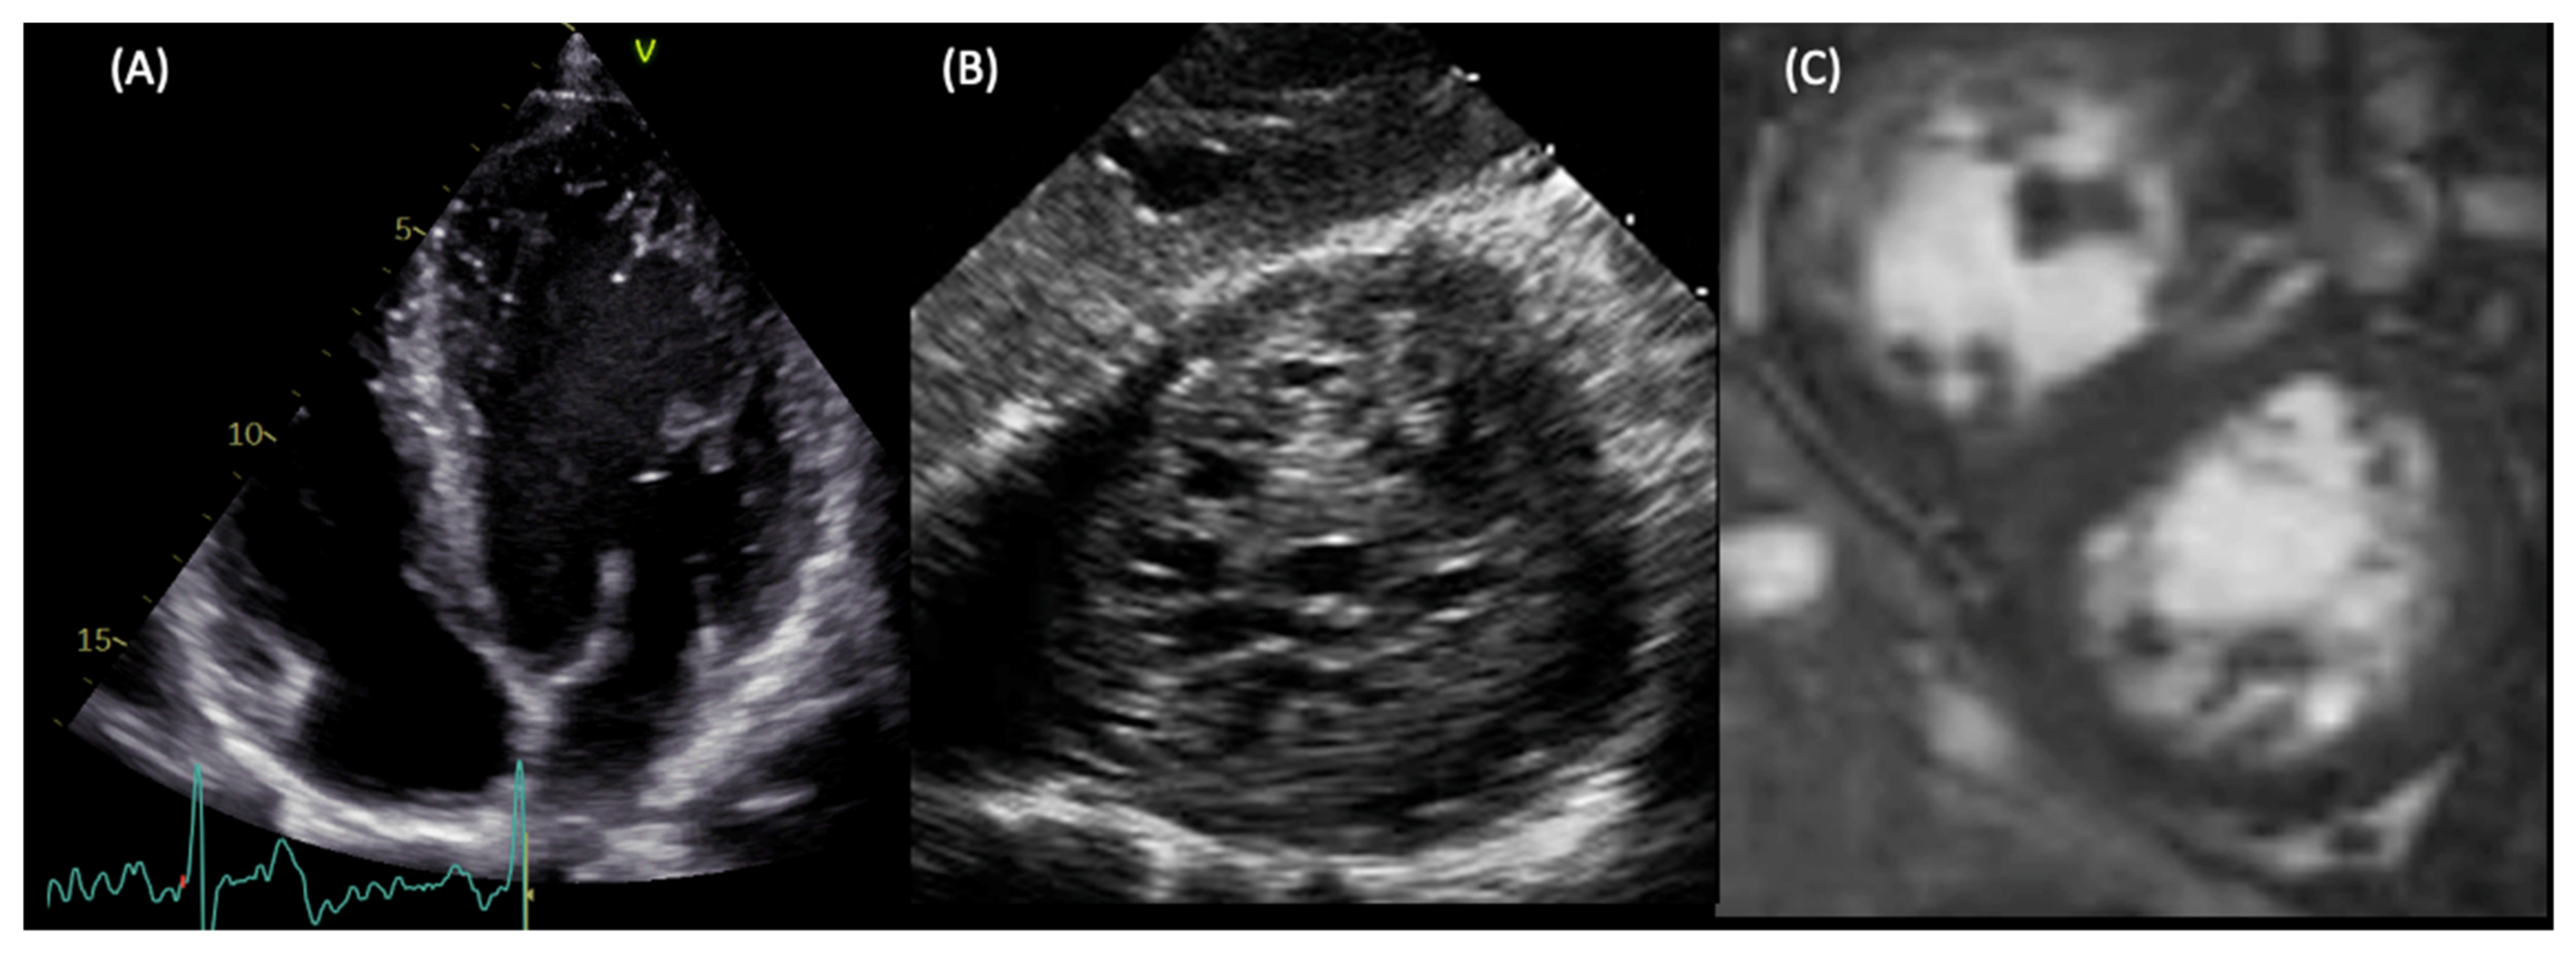

8. Clinical Presentation and Instrumental Findings at Diagnosis

9. Diagnosis

9.1. LVNC Diagnostic Criteria